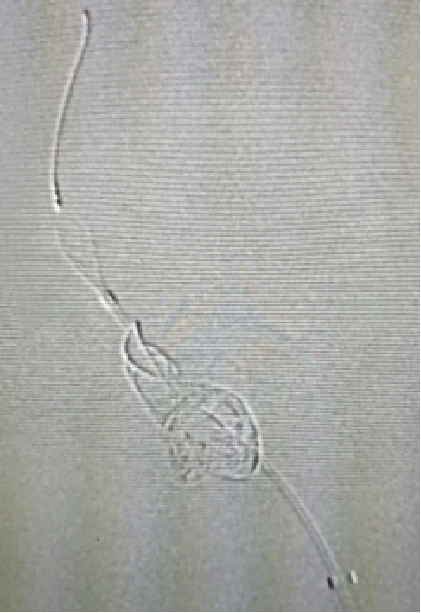

材料准备

双侧通路:右侧8F指引导管、5F navien

左侧6 8F指引导管

微导管:XT27、Rebar27、TJMC14

微导丝:Transend14

塑形:navien、XT27、Rebar27均J形

TJMC14大C形

Transend14 45°大J形

测量

5F navien对比

TJMC14测量长度

锚定过短,ped释放时掉动脉瘤内

Ped 3.5x30

木马技术:navien到达M1,ped带管到M1释放